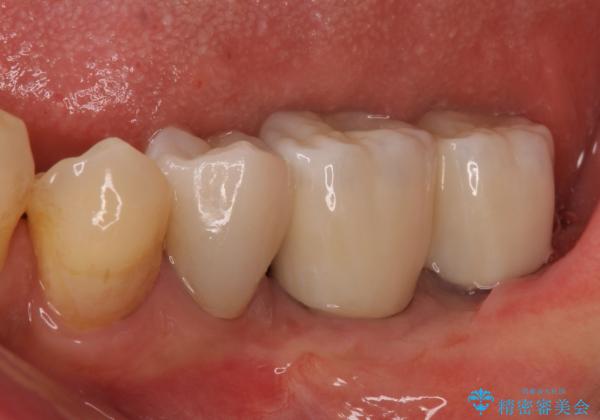

インプラント埋入後、手前のインプラント周りの丈夫な歯肉(角化歯肉)が失われてしまったため、角化歯肉の移植を行うこととなりました。

十分な角化歯肉が獲得でき、清掃性の高い環境が達成されました。